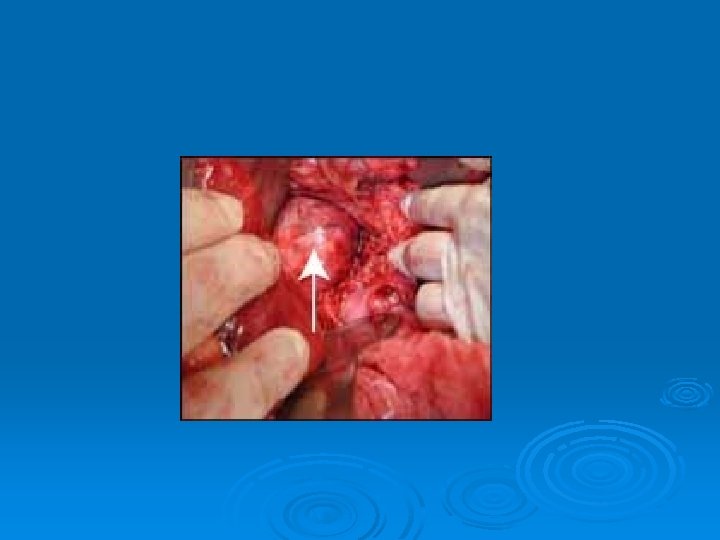

Minimally invasive parathyroid surgery

Minimaly inavsive parathyroid surgery Ø Ø Ø Videoendoscopic- co 2 insufflations Videoendoscopic- gassless Videoassisted Radioguided Focused central mini incision Focused lateral mini incision